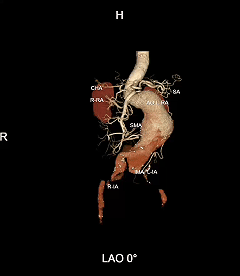

G-Branch是全球首创胸腹主混合多分支支架型血管系统,由中国人民解放军总医院第一医学中心郭伟教授与先健联合研发,专为TAAA设计,开创性实现内脏区分支全腔内重建的系统性解决方案。该产品于2025年11月获NMPA批准重磅上市,为全球患者带来了突破性的"中国解法”。

IV型胸腹主动脉瘤,瘤颈和双侧髂动脉严重扭曲,瘤体巨大,内脏分支血管开口角度倾斜

采用G-Branch胸腹主动脉覆膜支架隔绝瘤体,重建内脏区分支。主体使用TAAA3418120e7i1010,腹腔干和肠系膜上动脉分别植入直径10mm覆膜支架,右肾直径6mm支架,左肾直径7mm支架